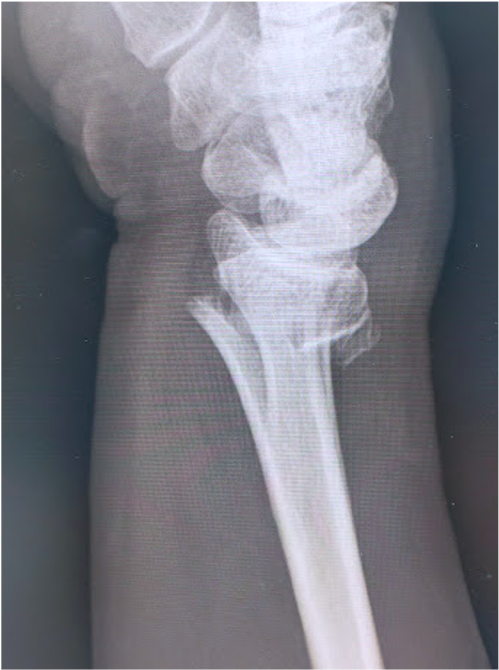

橈骨遠位端骨折に対する骨接合術